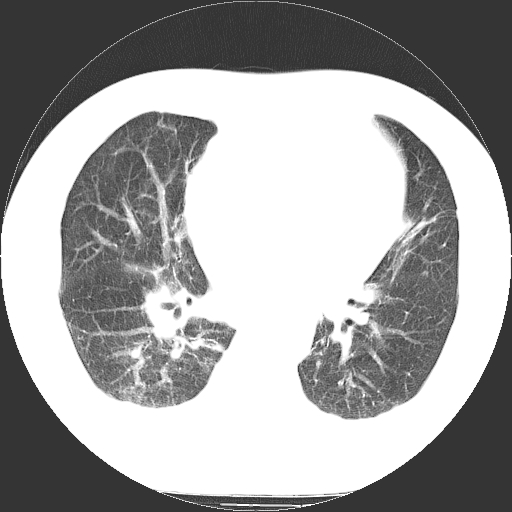

标题: CT21804:男,65岁,咳嗽、咳痰、发热5天。 [打印本页]

男,65岁,咳嗽、咳痰、发热5天。

慢支 肺间质纤维化合并感染!

支气管扩张合并感染,胸膜肥厚

考虑慢支并感染,肺间质纤维化。

两肺间质性炎症并感染

慢支,肺心病

支持慢性支气管炎伴感染,双侧少量胸腔积液.

两肺间质纤维化,支扩合并感染,双侧胸腔积液

感染,肺间质纤维化。

慢支 肺间质纤维化合并感染

支持慢性支气管、肺间质纤维化合并感染。

慢性支气管炎并感染,支扩,双侧少量胸腔积液.